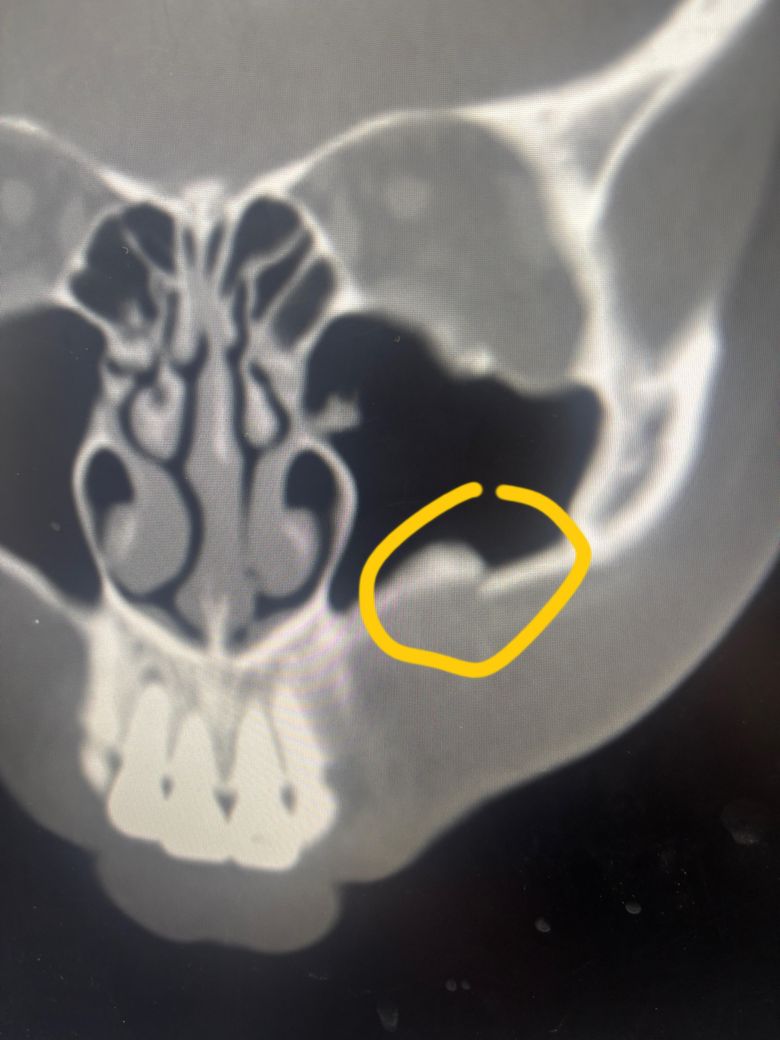

친구랑 어떤 남자랑 시비가 붙었는데 상대 남자가 제 친구 얼굴을 가격해서 제가 말린답시고 쓰레기 봉투 를 던졋는데 그러고 이 남자가 제 얼굴을 가격해서 왼쪽 코 뼈 골절 / 상악골 골절 / 광대뼈 골절 / 이빨 부서짐 . 흔들림 진단을 받았습니다.

2번째가 코 부분입니다